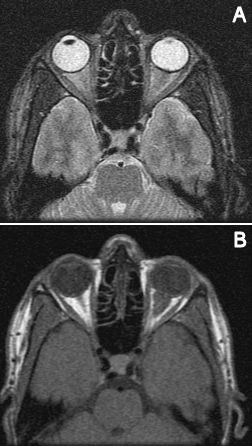

A 29-year-old Hispanic male presented with a week of blurriness in his left eye that progressed to complete vision loss. He was HIV positive for 6 years with a latest CD4 count of 100 and a viral load of 617 copies/mL on HAART therapy. He noted fevers and chills, but no other symptoms. On examination, the left pupil was fixed with no response to light. A reverse relative afferent pupillary defect was present in the right eye. The left optic nerve was edematous with blurring of margins. A CT scan showed enhancement of the retrobulbar optic nerve of the left eye with an adjacent, discrete soft tissue enhancement bordering the posterior globe (Figure 1 [Fig. 1]). Two weeks later, an MRI showed diffuse thickening and contrast enhancement involving the retrobulbar portion of the left optic nerve associated with a surrounding soft tissue lesion within the intraconal orbital fat, and the lesion seemed to be extending more posteriorly than the previous CT image (Figure 2 [Fig. 2]). The mass abutted the posterior aspect of the sclera. The lesion demonstrated low T1 and intermediate T2 signal intensities and heterogeneous contrast enhancement. There was also nodular contrast enhancement of the left optic nerve disc. The size of the lesion measured 17.4 mm x 15 mm x 10.6 mm. Cerebrospinal fluid studies were unremarkable. An anterior orbitotomy with exploration and biopsy of the left orbital mass was performed.

Figure 2: Magnetic resonance imaging showing a retrobulbar orbital mass in the left orbit

CT scans generally shows a well-defined, homogenous, high-density mass that is nodular and has distinct margins [8]. MRI usually shows hypointensity particularly on T1-weighted images and homogenous enhancement [9]. Most orbital lymphoid tumors tend to conform to structures around them without bony erosions. The MRI images of our patient do agree with some of these findings such as hypointensity on T1-weighted imaging; however, our patient’s lesion did show heterogeneous enhancement. Another rare feature is the intraconal position. Priego et al. estimated that 10.5% of orbital lymphomas have only intraconal involvement [10].